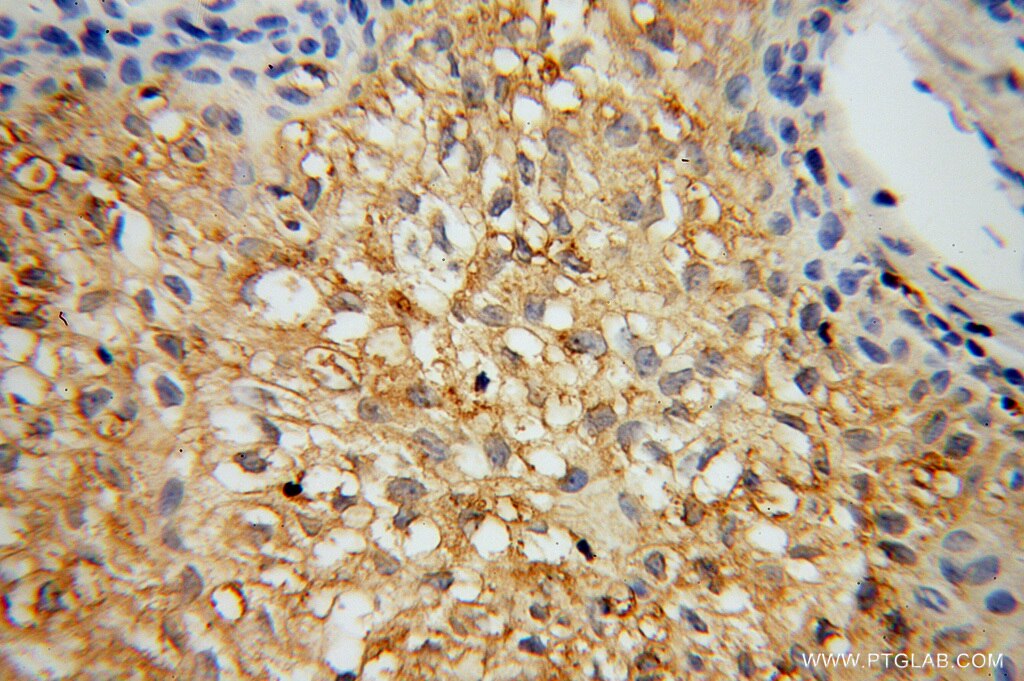

| Positive IHC detected in | human osteosarcoma tissue Note: suggested antigen retrieval with TE buffer pH 9.0; (*) Alternatively, antigen retrieval may be performed with citrate buffer pH 6.0 |

| Immunohistochemistry (IHC) | IHC : 1:20-1:200 |